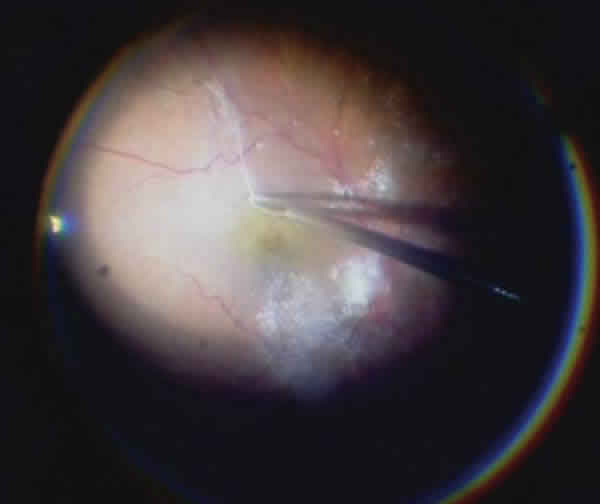

TB is a hydrophilic anionic azoic dye having the formula C34H24N6Na4O14S4 and a molecular weight of 960 daltons. It has been broadly used in vitrectomy and in cataract surgery. It can be obtained at a concentration of 0.15% for vitreous surgery under the Membrane Blue brand (DORC International, Zuidland, The Netherlands) and as Vision Blue at a concentration of 0.06% for cataract surgery (DORC).

Fig. 7: ERM staining with Triphan blue.

Both presentations include a formula comprising sodium salts, 8.2 mg of NaCl and water with an osmolarity between 257 and 314 mOsm/Kg, with a pH ranging between 7.7 and 7.6 TB exhibiting high affinity for ERM due to its dead glyal cell content and the fact that it does not stain the ILM as well as ICG. However, a comparative study on the ILM peeling ease in macular hole cases with ICG and TB, as well as the hole closure percentages, has demonstrated that the anatomic closure percentages were similar and that the visual result was significantly better in eyes stained with TB.

Fig. 8: ERM staining and peeling after Triphan blue injection.

Many researchers agree that this is an adequate dye for staining and eliminating ERM because it stains its entire surface in addition to reducing the retinal trauma during removal and facilitates the identification of its entire surface.

Most studies observed the absence of toxicity for the retina and the RPE, although one case was reported in which the dye migrated to the sub-retinal space, producing changes in the RPE without visual repercussions. The histopathology of extracted tissue did not show the presence of retinal cells or apoptotic tissue. Multifocal electroretinography did not reveal damages either, while electronic microscopy showed ILM remains adhered to the ERM, which also occurs when no dyes are utilized.